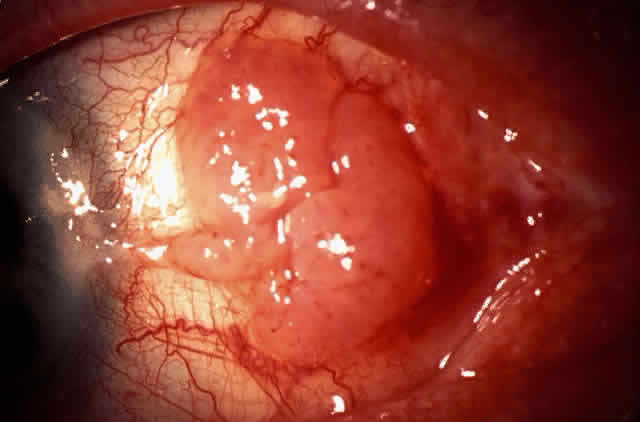

The epithelial dysplastic lesions—conjunctival intraepithelial neoplasia and squamous cell carcinoma—almost always begin at the limbus, most commonly in the interpalpebral zone.57,58 The initial appearance is a gelatinous, gray lesion with some thickening (Fig. 3). There may be increased vascularization. The epithelial changes may extend onto the cornea, causing a hazy, gray appearance. Tumor vascularity lags behind the lead margin of the epithelial change. As the lesions progress from dysplastic to carcinomatous, they become thicker, more vascularized and may show keratinization, giving a leukoplakic appearance (Fig. 4). Lesions confined to the epithelium move freely over the sclera, whereas invasive lesions are fixed to underlying tissue. Occasionally squamous cell carcinomas appear identical to classic papillomas.

|

|